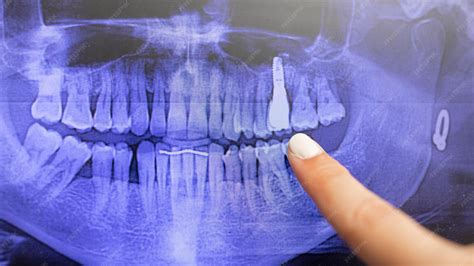

El tratamiento con implante de titanio comienza con una fase de evaluación y diagnóstico. En esta etapa, el dentista realiza un examen clínico completo, acompañado de radiografías o estudios de imagen como un TAC 3D, para analizar el estado del hueso y la salud bucal del paciente.

Cuando la integración del implante es satisfactoria, se procede a colocar el pilar o conector, que une el implante con la prótesis definitiva. Sobre este pilar se coloca finalmente la corona dental, que es la parte visible del diente.